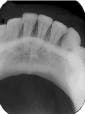

The bisecting-angle technique creates specific errors in vertical angulation, giving shortened images (see Radiograph 2 as an example of foreshortening) or lengthened images (see Radiograph 3 as an example of elongation). Substantially shortened images occur because there is too much vertical angulation. This causes distortion in the reproduction of the actual size of the tooth. The solution requires a decrease of the vertical angulation by at least 10 degrees.

Conversely, lengthened im-ages occur because there is not enough vertical angulation. Another reason is that the film is curved in the mouth. Increasing the vertical angulation by at least 10 degrees and repositioning the film to prevent bending will alleviate this distorted image.